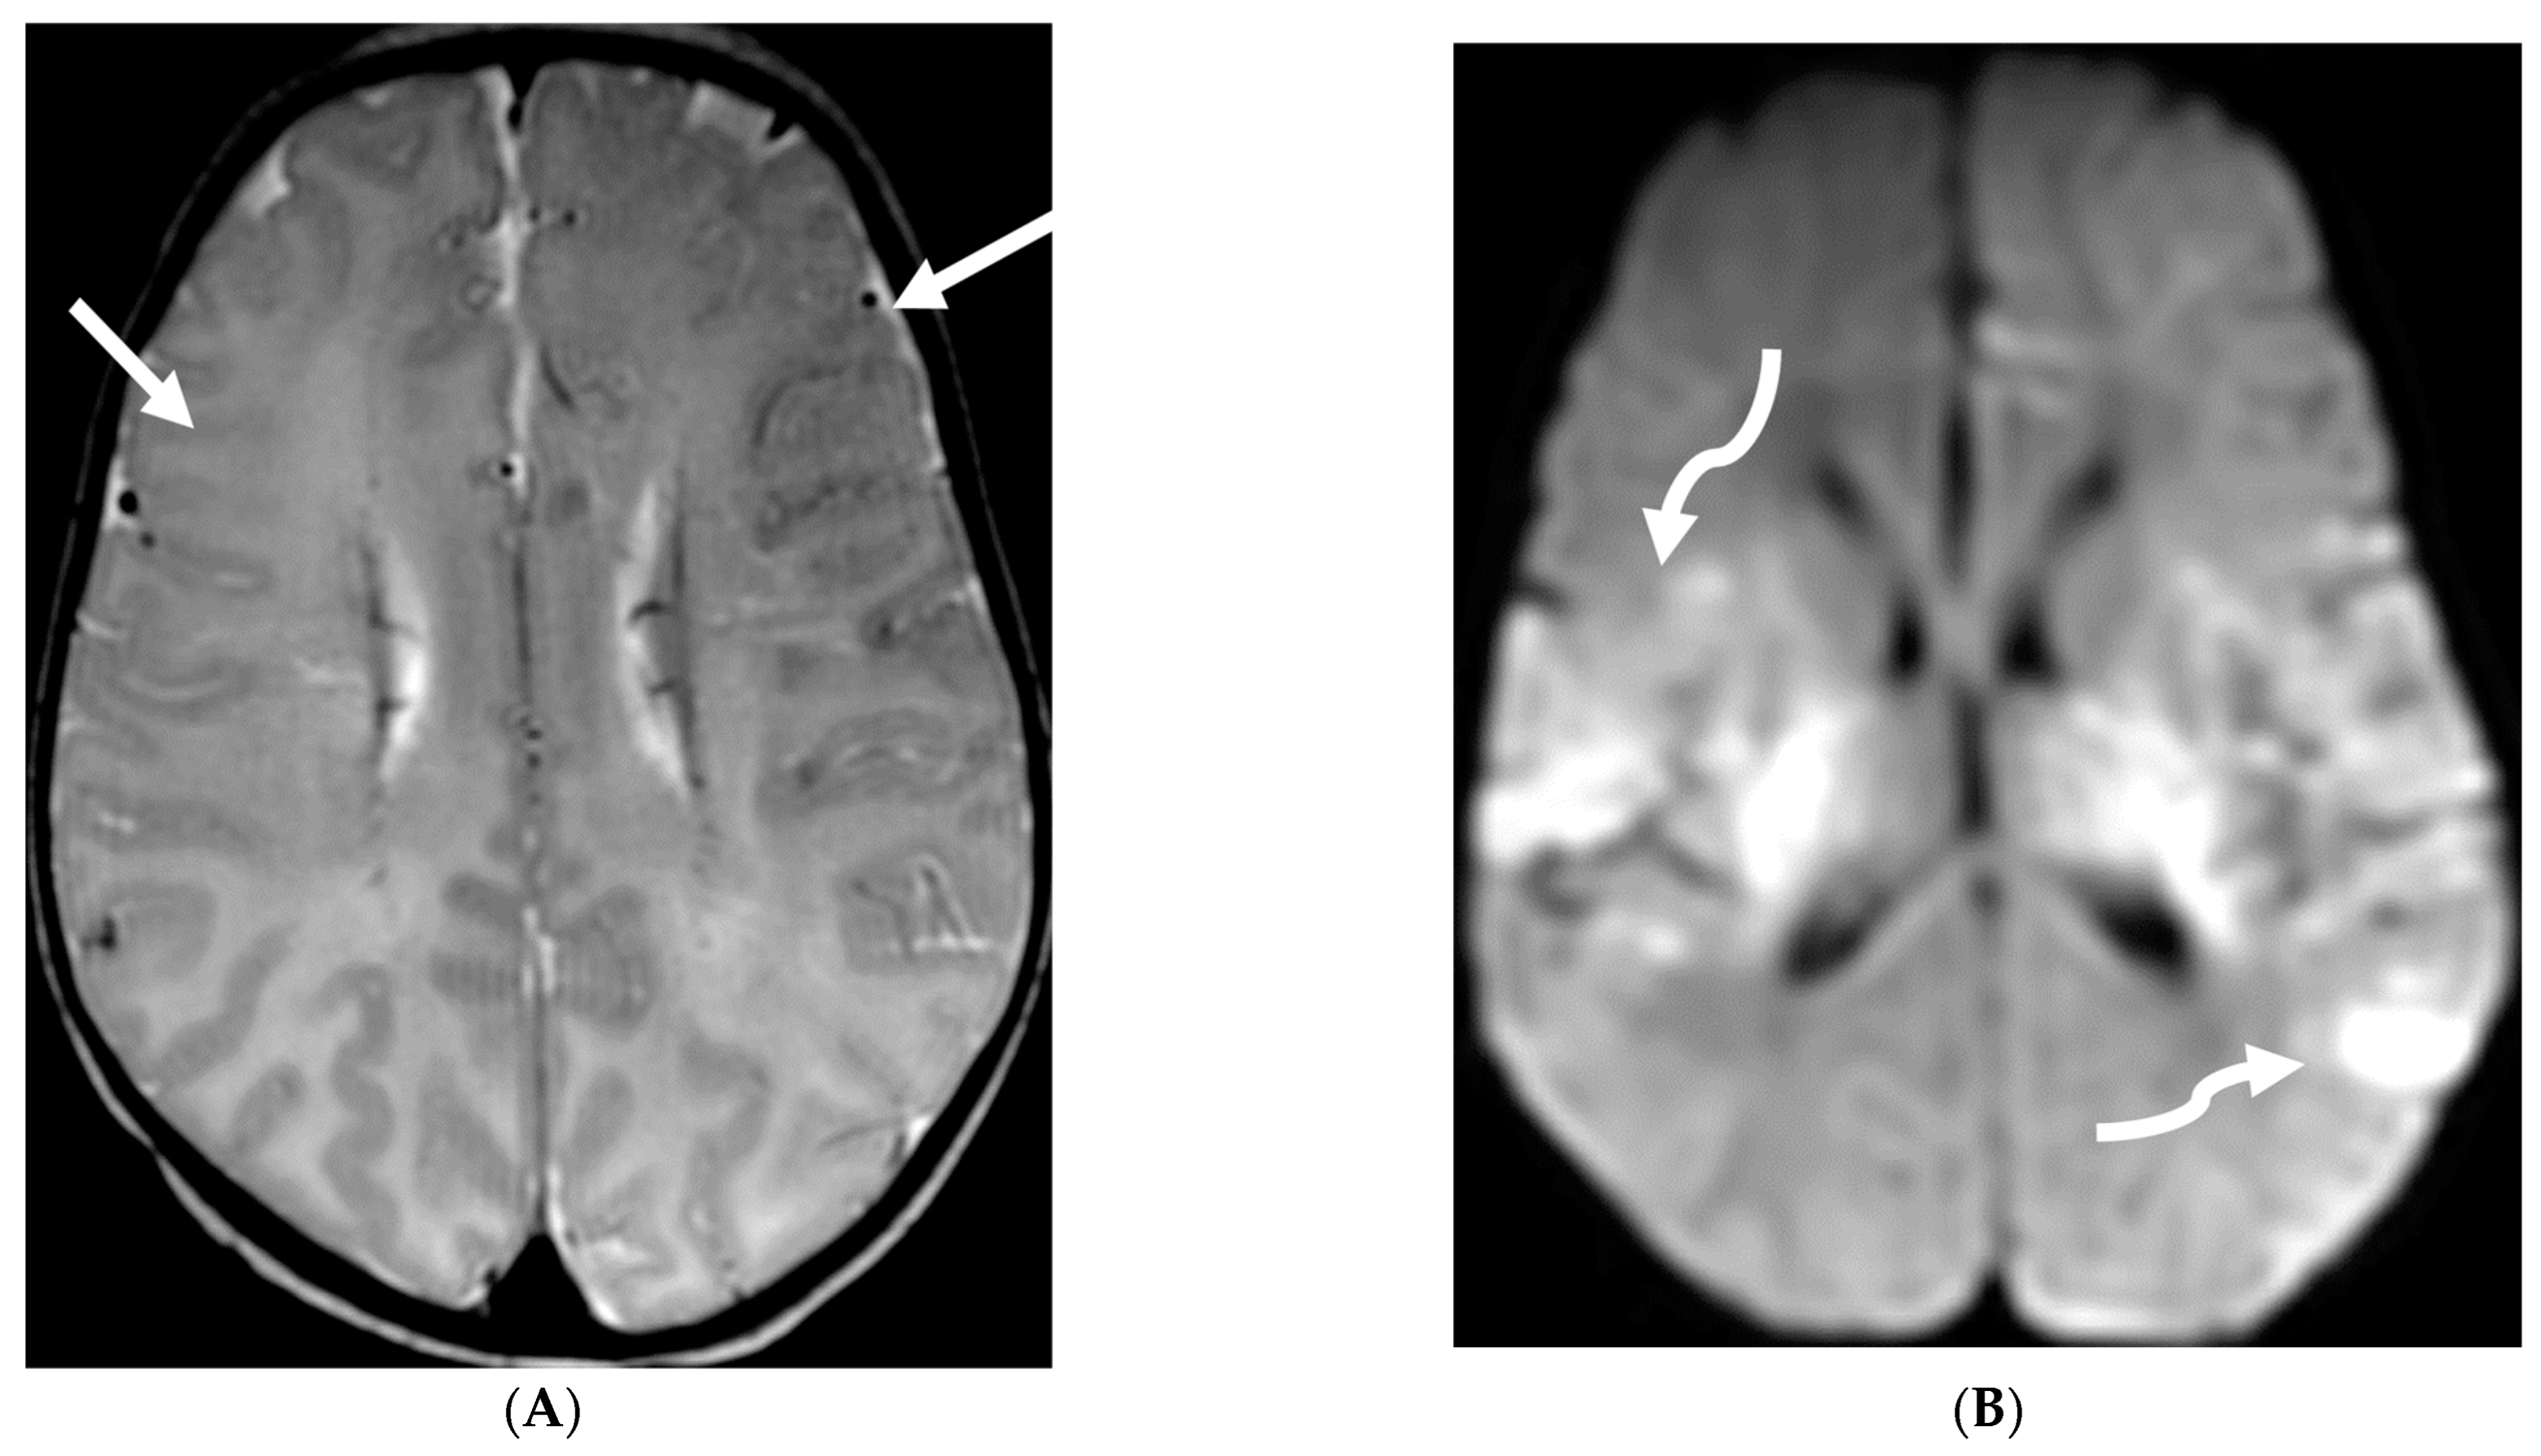

Meningeal metastases from an extracranial primary tumor is a diagnosis with a grave prognosis, reducing the survival to less than 3 months if left untreated. Early and accurate diagnosis is essential for improving patient outcomes [84]. Leukemias and neuroblastoma are the most common primary malignancies in the pediatric population [85,86]. Leukemia is the only one which merits prophylactic treatment to avoid SMM.

The typical MRI presentation of SMM involves serpentine, nodular, or plaque-like enhancement in sulcal spaces, basal cisterns and along the cauda equina nerve roots [87,88]. Notably, SMM enhancement on post contrast [PC]-T1 images is superior to the PC-FLAIR in contrast to that seen in infectious meningitis [84]. However, in case of a non-enhancing primary tumor, FLAIR and DWI are important sequences to look for SMM. Hydrocephalus and subependymal deposits are other common features found in kids with SMM (Figure 15, Figure 16 and Figure 17). Positive cytology on CSF analysis, especially with leukemia, is important [89].

Figure 15.

Axial DWI (A), axial ADC (B), axial T1 FS post contrast (C) and Fluorodeoxyglucose Positron Emission Tomography (FDG–PET) scan (D): 13-year-old male with bilateral leg pains, headache, fever and weight loss: Blood tests and CT scan were concerning for Burkitt’s lymphoma. There is heterogeneous calvarial bone marrow signal with restricted diffusion (arrows) and patchy enhancement (curved arrows). Diffuse thickening and enhancement of pachymeninges in the supratentorial compartment is noted (dashed arrows). Findings are most consistent with lymphomatous involvement. Multifocal diffuse/heterogeneous pattern of FDG uptake within the axial and appendicular skeleton and the calvarium (open arrows). Intense FDG avid uptake is seen in the presacral mass (star).

Figure 16.

16-year-old female with 4 months history of globus sensation and recent botox injection of lower esophageal junction. Headache and vomiting for past week: Esophagogram (A), Axial T2 orbits (B), axial FLAIR (C) and post contrast T1 (D,E): Narrowing of the Gastroesophageal (GE) junction with beaked configuration and mild distention of the lower esophagus likely from early achalasia (black arrow). There is bilateral papilledema indicating raised ICP (dashed arrows) and sulcal hyperintensity (curved black arrows). Diffuse LME in the supra-and-infratentorial regions and along optic sheaths raising the concern for leptomeningeal carcinomatosis (white arrows). Pathology: Gastric adenocarcinoma metastasis.

Figure 17.

Axial T2 FS (A), axial Susceptibility weighted imaging (SWI) (B), axial DWI (C), post contrast sagittal and axial T1 post contrast (D,E): 19-year-old female with history of stage IV neuroblastoma, left paraspinal primary ganglioneuroblastoma, treated with chemotherapy, radiation and bone marrow transplant presents with headache. There are extensive hemorrhagic leptomeningeal masses, both supra and infratentorial region (arrows). The lesions also demonstrate restricted diffusion which could be secondary to internal hemorrhage or high cellularity of the tumor(curved arrows). The larger masses invade the cortex of both cerebral hemispheres, with surrounding vasogenic edema (black arrow). Avid enhancement of the lesions is seen along with overlying dura (dashed arrows). Features are in keeping with extensive leptomeningeal metastatic neuroblastoma.